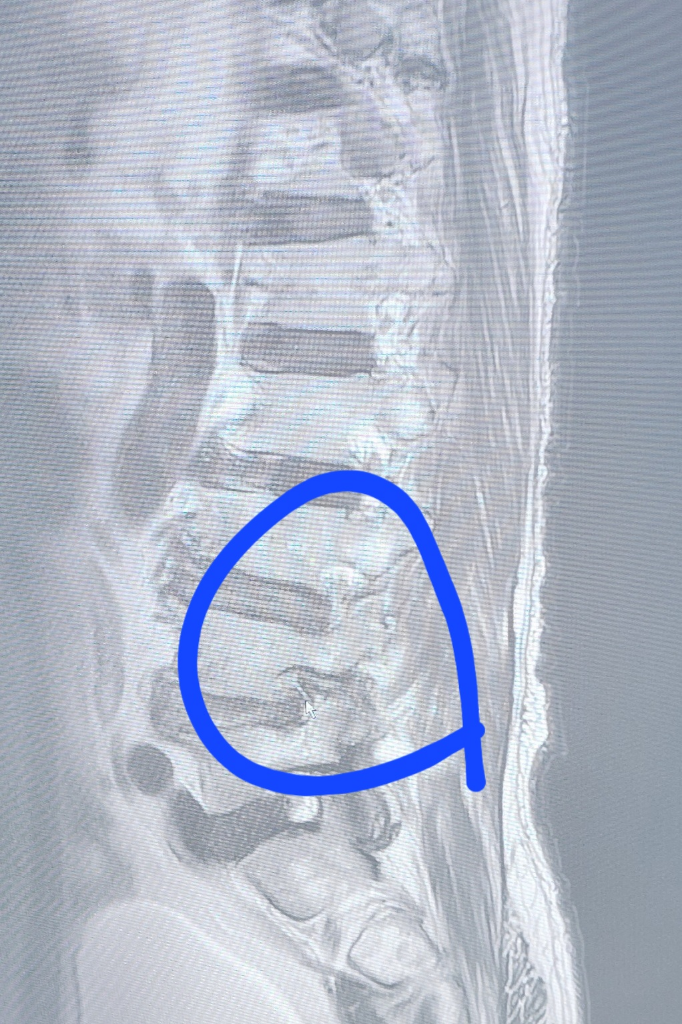

부모님 허리 상태 사진 봐주세요 디스크가 심한 편인가요?

부모님이 병원 다녀오시고 엠알아이 찍은 사진 보내 주셨는데 지금 체크된 부분이 디스크 협착 파열 되신게 맞으신건지요?

디스크 몇번인지 알려주시면 감사하겠습니다

• 2번 째 사진

현재 심한 병변 부위는 요추 3-4번 사이 추간판의 가능성이 있습니다. 사진과 별개로 신경학적 증상이 있다면 필요시 응급 감압술이 필요할 수도 있으므로 진료를 본 담당의사와 상의하는 것이 가장 정확합니다.

현재 MRI단면상으로 정확한 진단은 어려움이 있지만 요추 3-4번의 디스크 탈출증 및 요추 4-5번의 협착증이 관찰됩니다.

우선 마비 증상 등이 없으신 상태라면 신경차단주사 및 약물요법을 시행하시면서 경과관찰을 해보시는 것이 좋겠습니다.